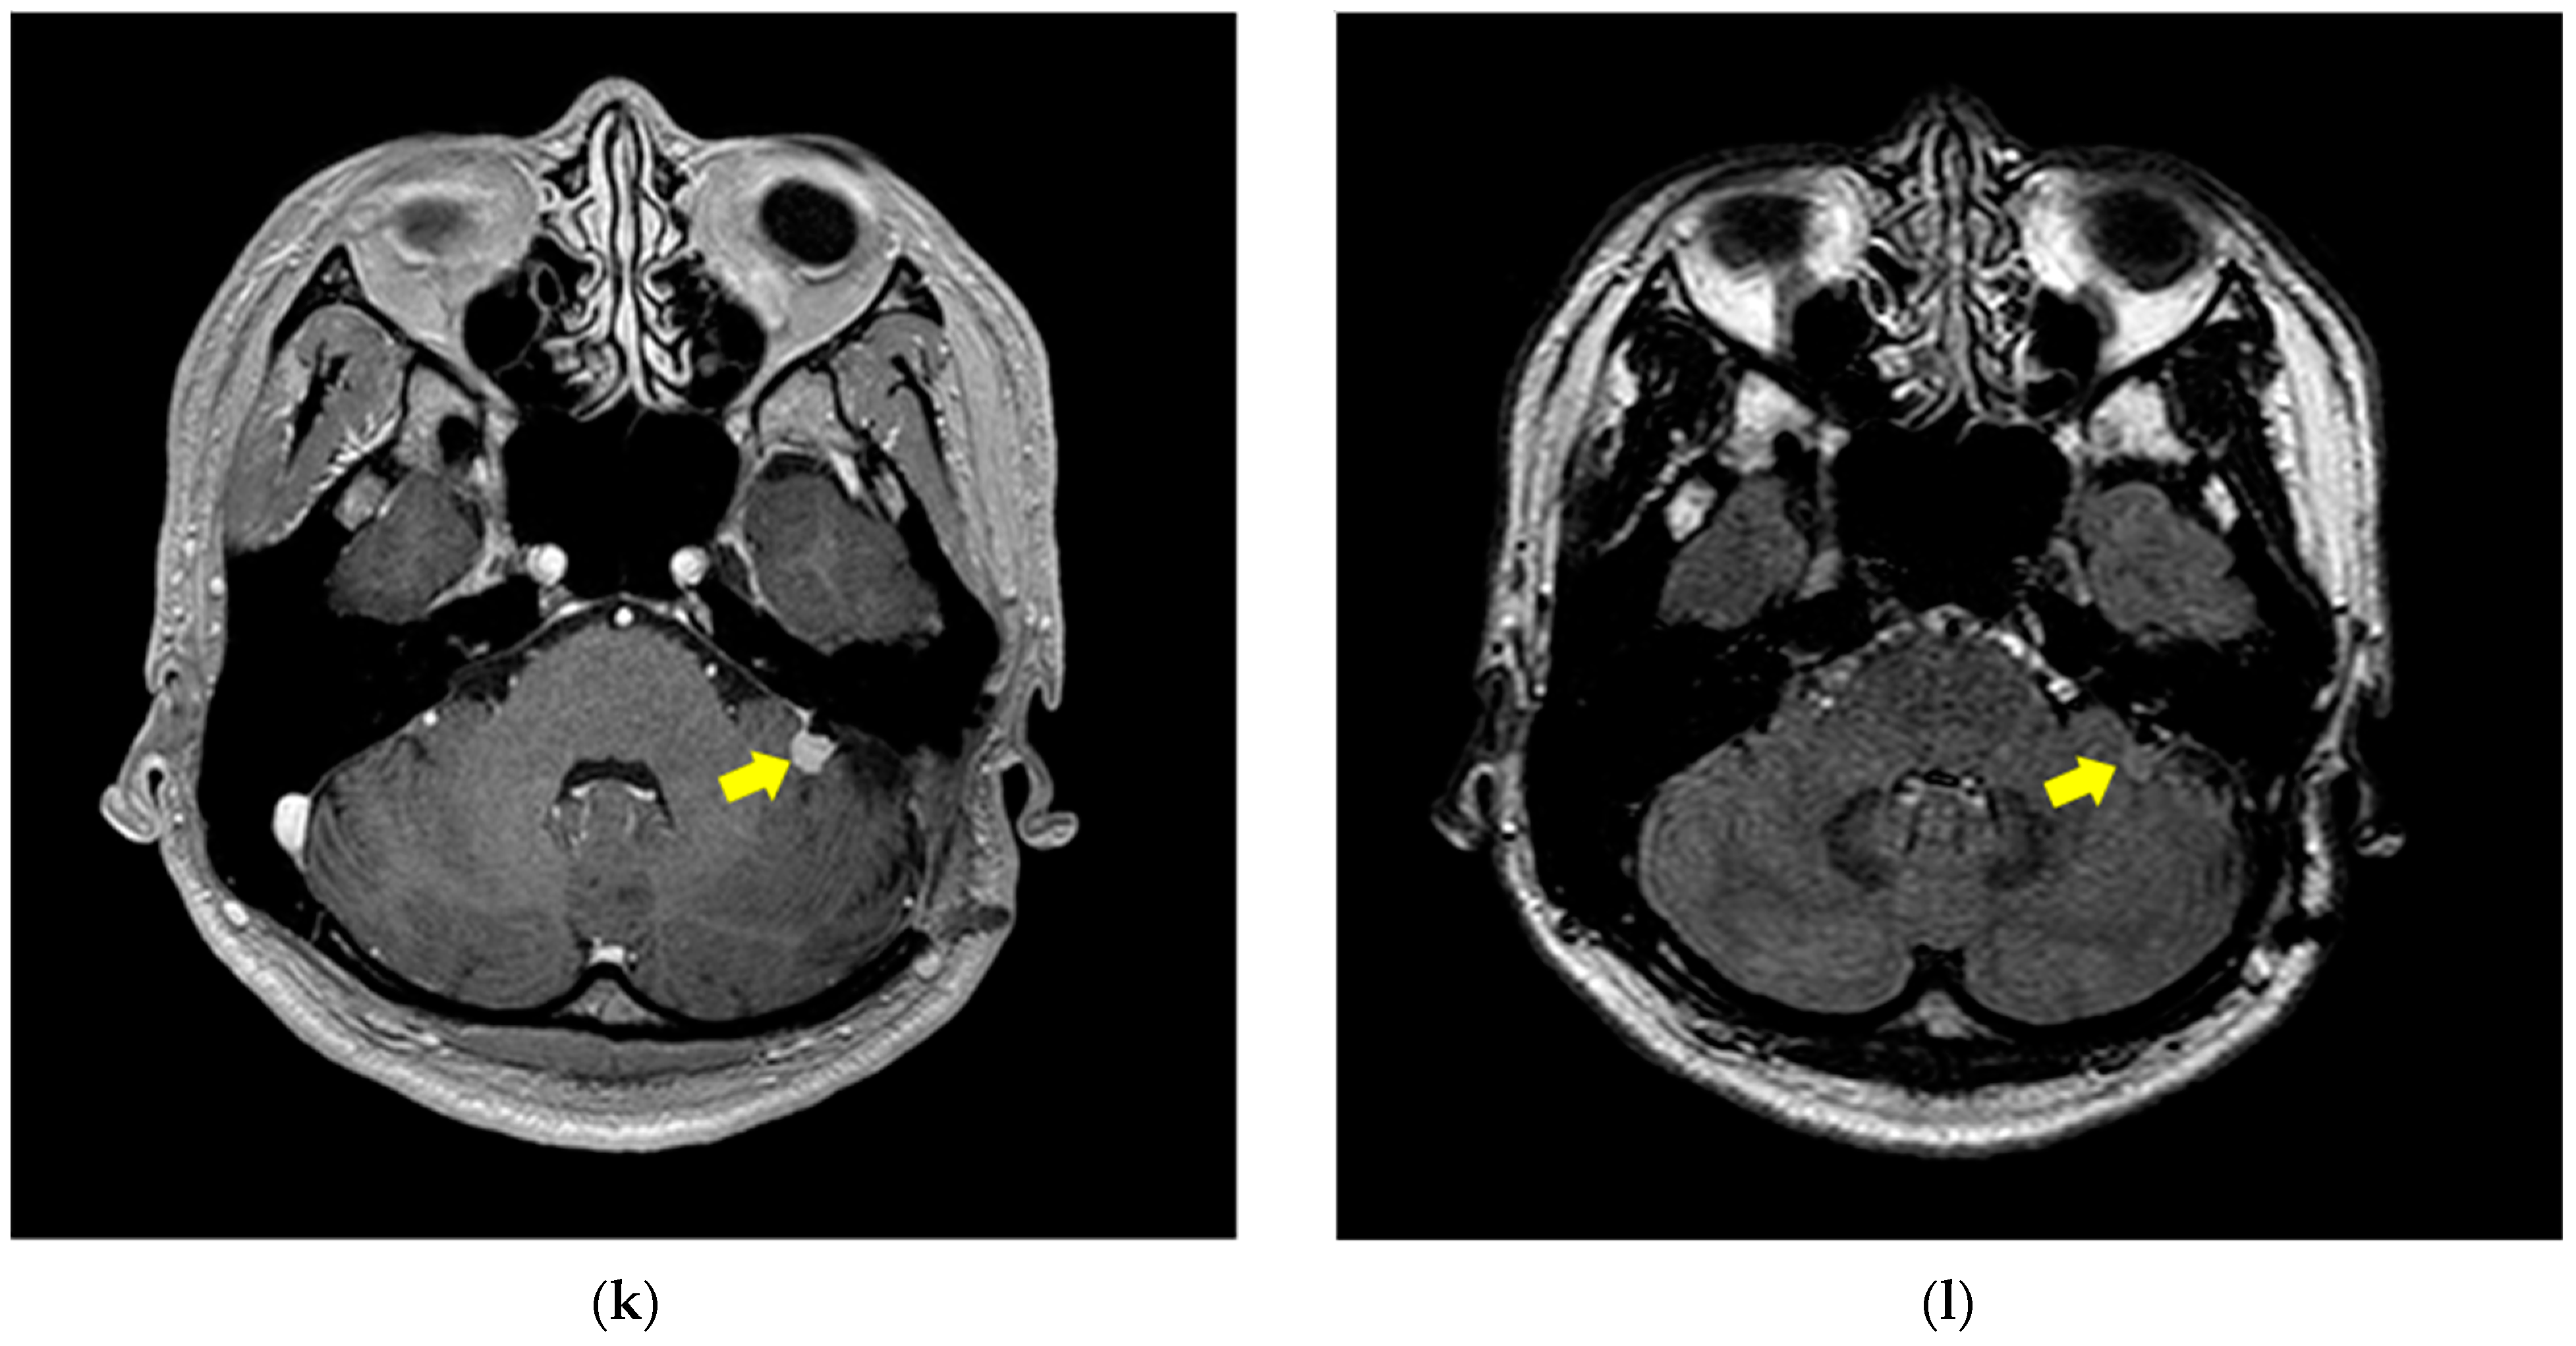

2.1. MRI Dataset

3.1. Image Pre-Processing